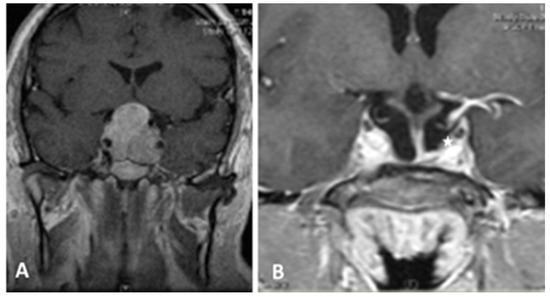

Among the 96 patients included, 55 were men (57.3%) and 41 were women (42.7%), and the mean age was 52.2 years (range 26–81 years). Gender and age were not significantly associated with EoR rate (p = 1.763) or hospital length of stay. Mean cranio-caudal diameter of lesion was 46.5 mm (range 41–61 mm). According to Knosp [8] grading scale, 30 (31.2%) were classified as grade 0; 24 (25.0%) grade 1; 19 (19.8%) grade 2; 9 (9.4%) grade 3 and 14 (14.6%) grade 4. Endocrinological screening confirmed the non-functioning status in all patients included in the study. Seventy-eight patients (81.2%) presented with visual field defects, 9 of whom (9.4%) also had visual acuity impairment. Fifty-three patients (55.2%) presented with various degree of anterior pituitary insufficiency: 27 had panhypopituitarism, 14 had combined corticotropic and thyrotropic insufficiency, 6 had isolated corticotropic insufficiency, 3 had isolated thyrotropic insufficiency and 3 isolated gonadotropic insufficiency. Twelve patients (12.5%) had headaches and 3 (3.1%) presented drowsiness associated with hydrocephalus. According to intraoperative assessment of lesion consistency, 50 GPAs (52.1%) were soft, whereas 46 GPAs (47.9%) were firm/fibrous. Thirty-one GPAs (32.3%) were deemed to have significant vascularization due to profuse intraoperative bleeding impairing visualization through the endoscopic lens and requiring more than 20 mL of advanced hemostatic matrix, whereas the remaining 65 GPAs (67.7%) did not. Interestingly, our results are in keeping with the data reported by previous studies [11,12], confirming that 2/3 of GPAs are not highly vascularized. EoR was classified as follows: GTR in 34 cases (35.4%) (Figure 1), NTR in 12 cases (12.5%) (Figure 2), and STR in 50 (52.1%) (Figure 3 and Figure 4).

Figure 1. T1- weighted contrast-enhanced MR images. Preoperative sagittal (A) view showing a giant pituitary macroadenoma, Knosp grade 1. Three-month postoperative coronal (B) and sagittal (C) views showing GTR. GTR: gross total removal.